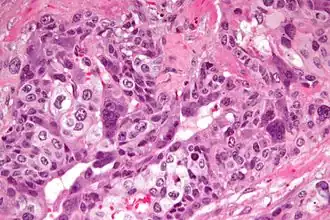

Хориокарцинома

Хориокарцинома — трофобластический рак, обычно плаценты. Он относится к злокачественному концу спектра при трофобластической болезни. Хориокарцинома также классифицируется как опухоль зародышевой клетки и может возникать в яичке или яичнике.